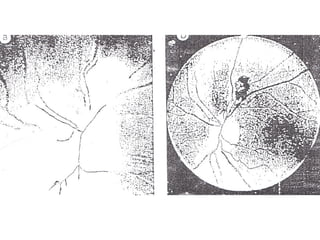

• Toxoplasmosis ocular: La retinocoroiditis es casi

siempre secuela de una infección congénita, los

síntomas son: visión borrosa, dolor muscular,

fotofobia, escotomas y epifora.

• Toxoplasmosis ocular:La retinocoroiditis es casi siempre secuela de una infección congénita, los síntomas son: visión borrosa, dolor muscular, fotofobia, escotomas y epifora. • Toxoplasmosis en pacientes inmunocomprometidos: Es el resultado de la reactivación de una infección crónica adquirida previamente al estado de inmunosupresión. Amplia diseminación de toxoplasma que puede ser fatal: afección del sistema nervioso central, fiebre elevada, neumonia, erupción cutánea, hepatoesplenomegalia, miocarditis, miositis, orquitis.